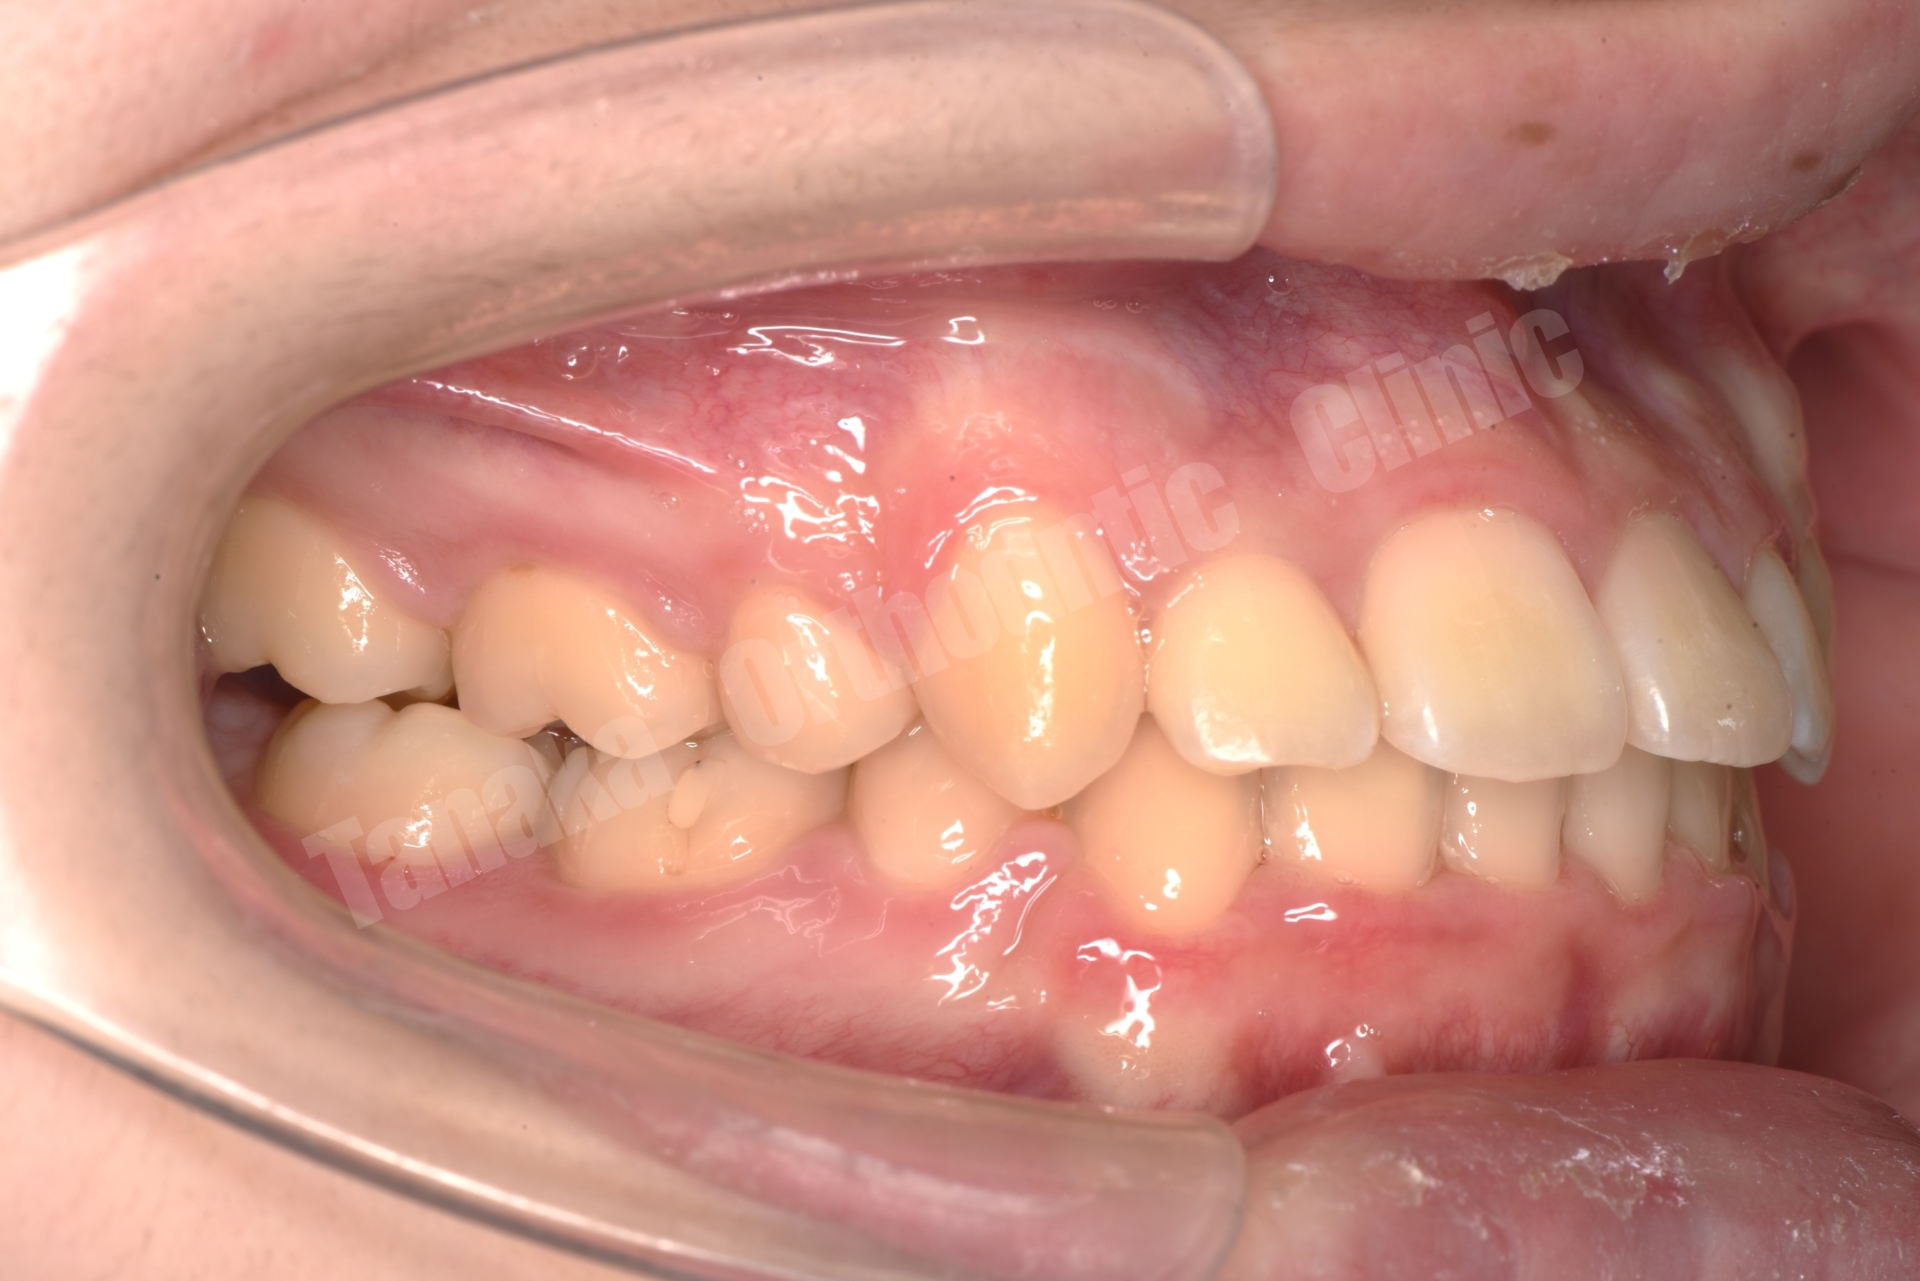

| 主訴 | 八重歯(13.23)、上顎正中の右偏位、下顎前歯のガタガタ |

| 診断 | 下顎前突(上顎後退傾向&下顎前突傾向)、上下顎歯列の叢生(上顎右側3番完全唇側転位&上顎正中の右偏位)、上下左右8番を認める |

Angle分類:Ⅰ〜Ⅱ級傾向

Skeletal:SKⅢ級傾向(上顎後方位+下顎前方位)

骨格性Ⅲ級傾向に加え、前歯のフレアと叢生、正中偏位が問題点でした。